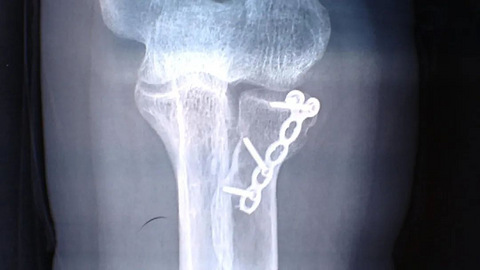

健身房摔倒索赔!高收入阿姨:赔我10万!经理:走法律程序

为了健康,不少人到健身房去锻炼。市民俞女士去健身房,不小心摔倒了,把手肘撑断了,现在手是养好了,但是她要求健身房赔10万,但是经理不同意。 2021年5月14号下午俞女士到奥世健身房游泳,在台阶上滑倒了,她下意识地双手撑地。而俞女士快50岁了,这一摔摔得不轻。 俞女士:他们台阶上没有铺防滑垫,所以很滑,我小心翼翼地走滑倒了,我当时一摔,我自己两个手臂都动不了了,我当时也糊涂了。 俞女士

玲玲玲叮当 2022-10-13 08:268648 14